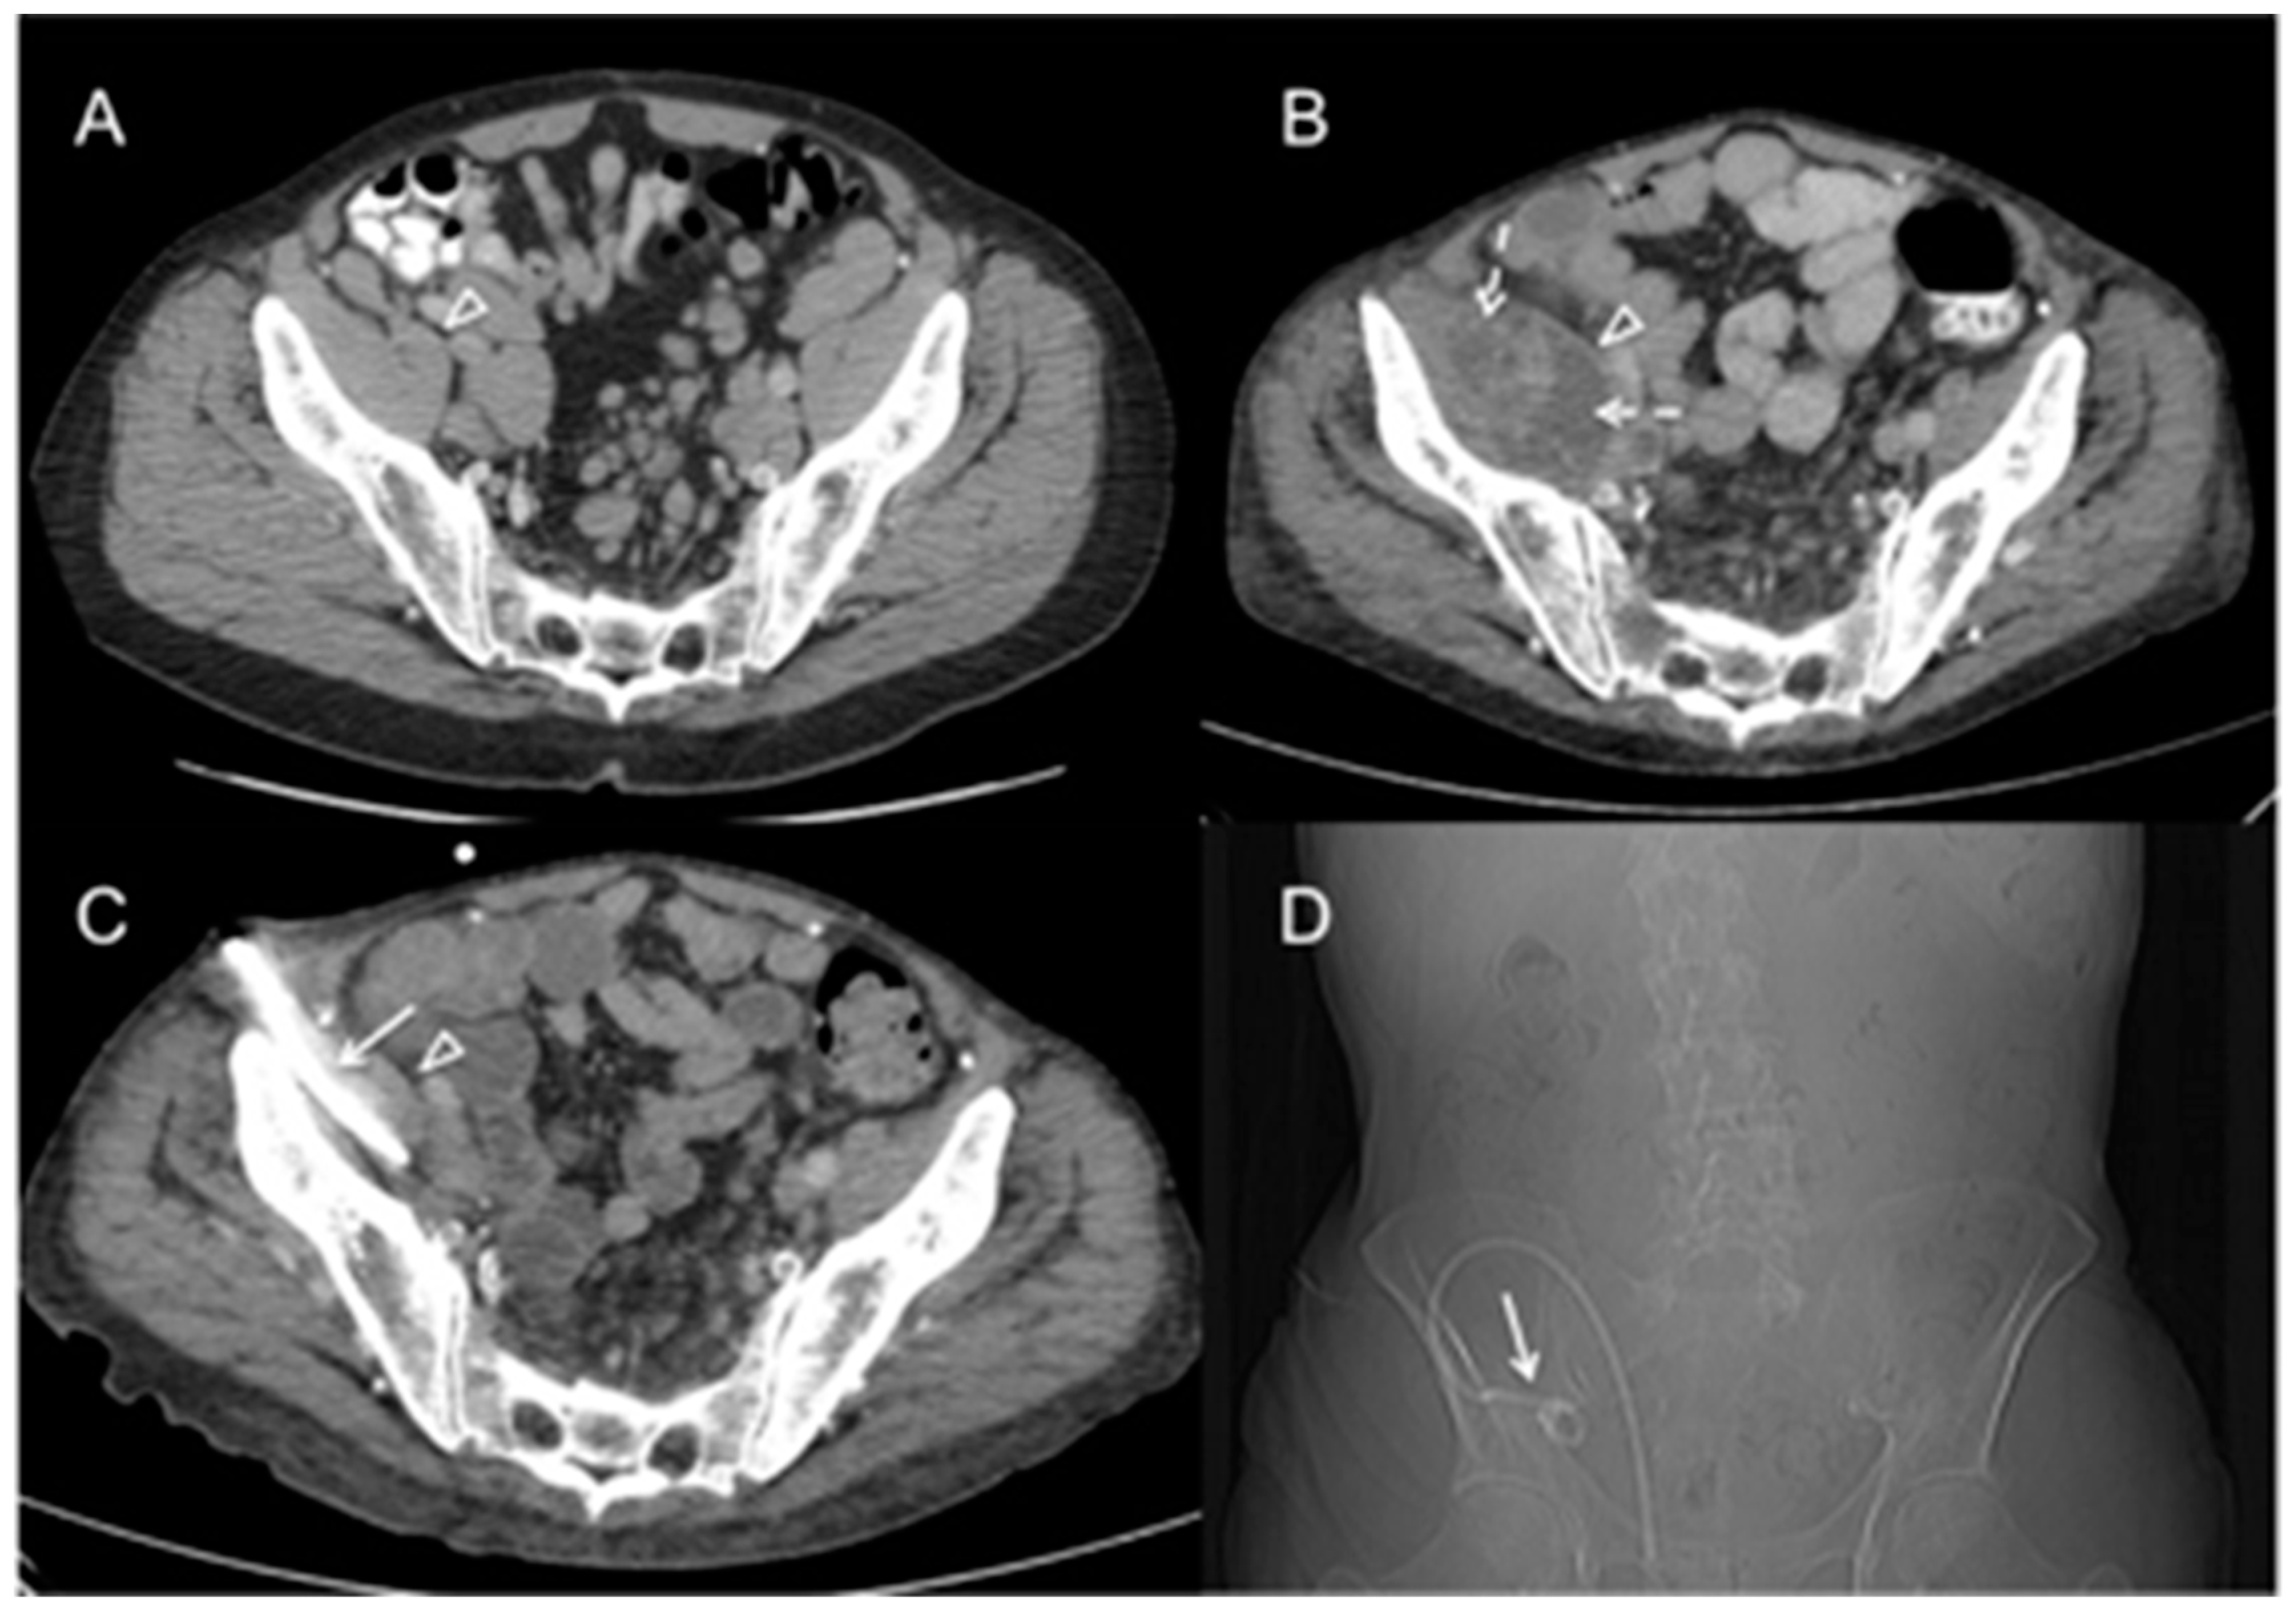

| 60 | 74 | Male | retroperitoneal and inguinal lymphadenitis, psoas abscess | Inguinal lymph node biopsy | chlorambucil, prednisone, fludarabine, rituximab, cyclophosphamide, bendamustin, ofatumumab, lenalidomide; intravenous immune globulin; obinutuzumab | MAC successfully treated, patient dies several months later | present case |